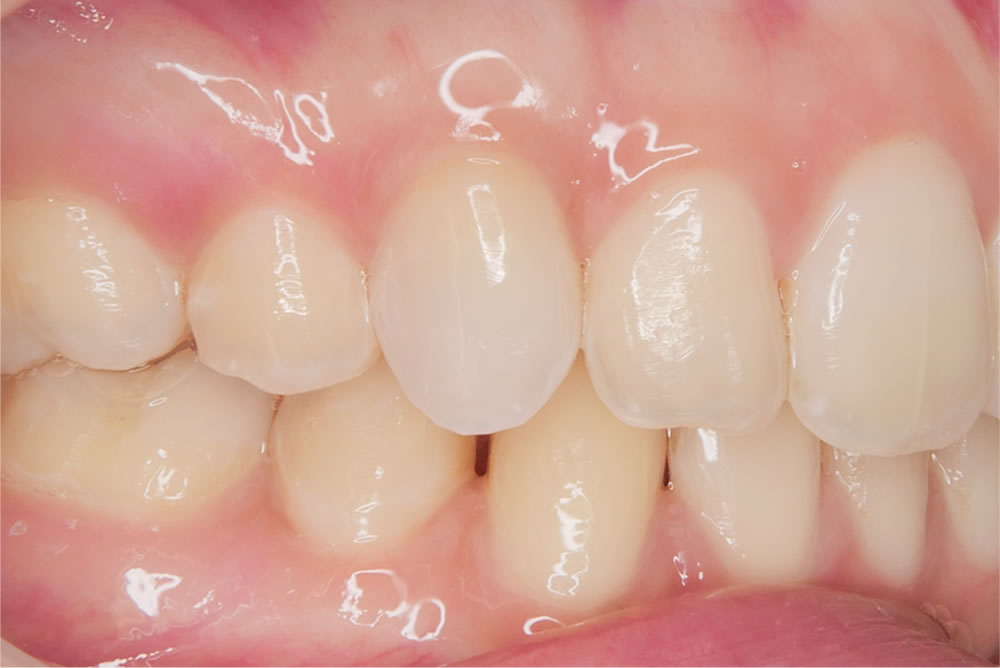

こちらの患者さんは、右上の前歯の色が黒くなってきたことを主訴に来院されました。

写真の通り、この歯だけが変色しており、他院では「削って被せ物にする必要があるかもしれない」と説明を受けていたそうです。

当院ではまず原因を調べるために各種検査を行いました。その結果、右上の前歯は冷たい刺激に反応せず、神経が死んでしまっている(失活歯)と判断しました。

原因として考えられたのは、過去に行われた矯正治療です。歯の根が骨の外に出てしまっており、本来は骨の中に位置すべき歯根が露出していたため、神経がダメージを受けてしまったと考えられます。通常、歯は骨のアーチの中に適切にコントロールして並べることが非常に重要で、それを外れてしまうと神経が死んでしまうリスクが高まります。